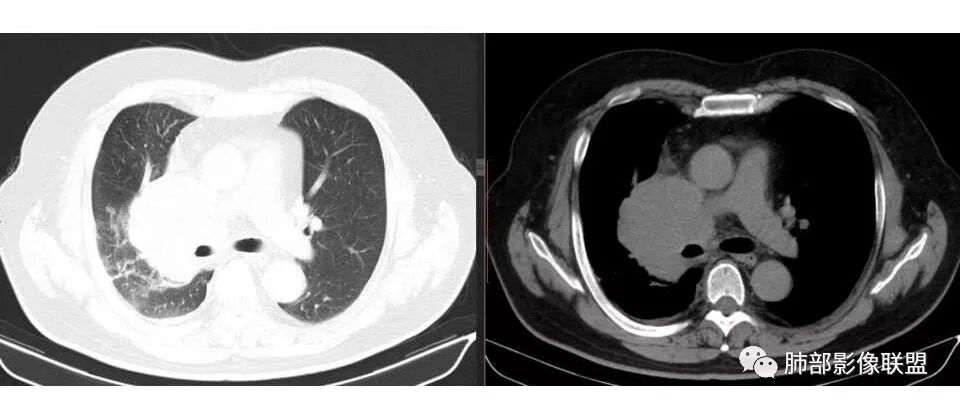

南边: 而且肺癌,一定受叶段的局限,这一例跨越右肺门,提示多个淋巴结融合

南边: 例如这个病灶,如果是一个孤立的肿块,边界清晰,提示破坏性不强,不应该是包绕支气管,是推移到一边为主,这个表现为包绕,提示是多个病灶融合

宇宙星空: 肺门区及纵隔淋巴结肿大融合,支气管被包绕

宇宙星空: 支持南大的分析,简单总结为:冰冻纵隔,娘小崽大,右肺小结节,支持小细胞

1.右肺上叶不规则结节影,右肺门及纵隔多结节并形成巨大块影,密度均匀,沿途支气管明显狭窄。

原发灶小或隐匿,肺门纵隔淋巴结异常增大,所谓“娘小崽大”常见于肺小细胞癌!